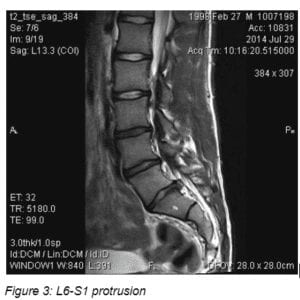

Magnetic Resonance Imaging (MRI) Imaging was available at the January visit and demonstrated prominent protrusions at two levels. See Figures 2 to 4

The physical therapists and pain physician helped the parents identify an appropriate pediatric surgeon at a well-known medical center in a large metropolitan area. A consult was obtained within 2 weeks. The surgeon requested a 6-week trial of 15 mg. oral Meloxicam. This brought no change in symptoms and laminotomy and microdiscectomy on left L5-L6 and right L6-S1 surgery was performed in March 2015.